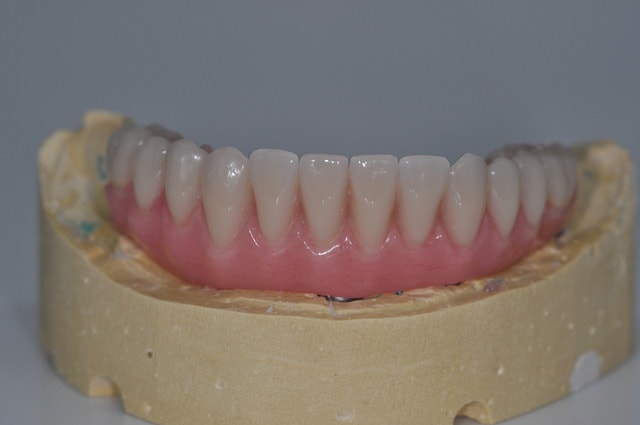

Mon premier complet immédiat sur implants fait cette semaine...

Implants posés mercredi matin, bridge posé jeudi matin...

Dsc 0037 clomyw - Eugenol

Dsc 0038 cff4sp - Eugenol

Dsc 0039 n8y16y - Eugenol

Dsc 0040 vdb4vc - Eugenol